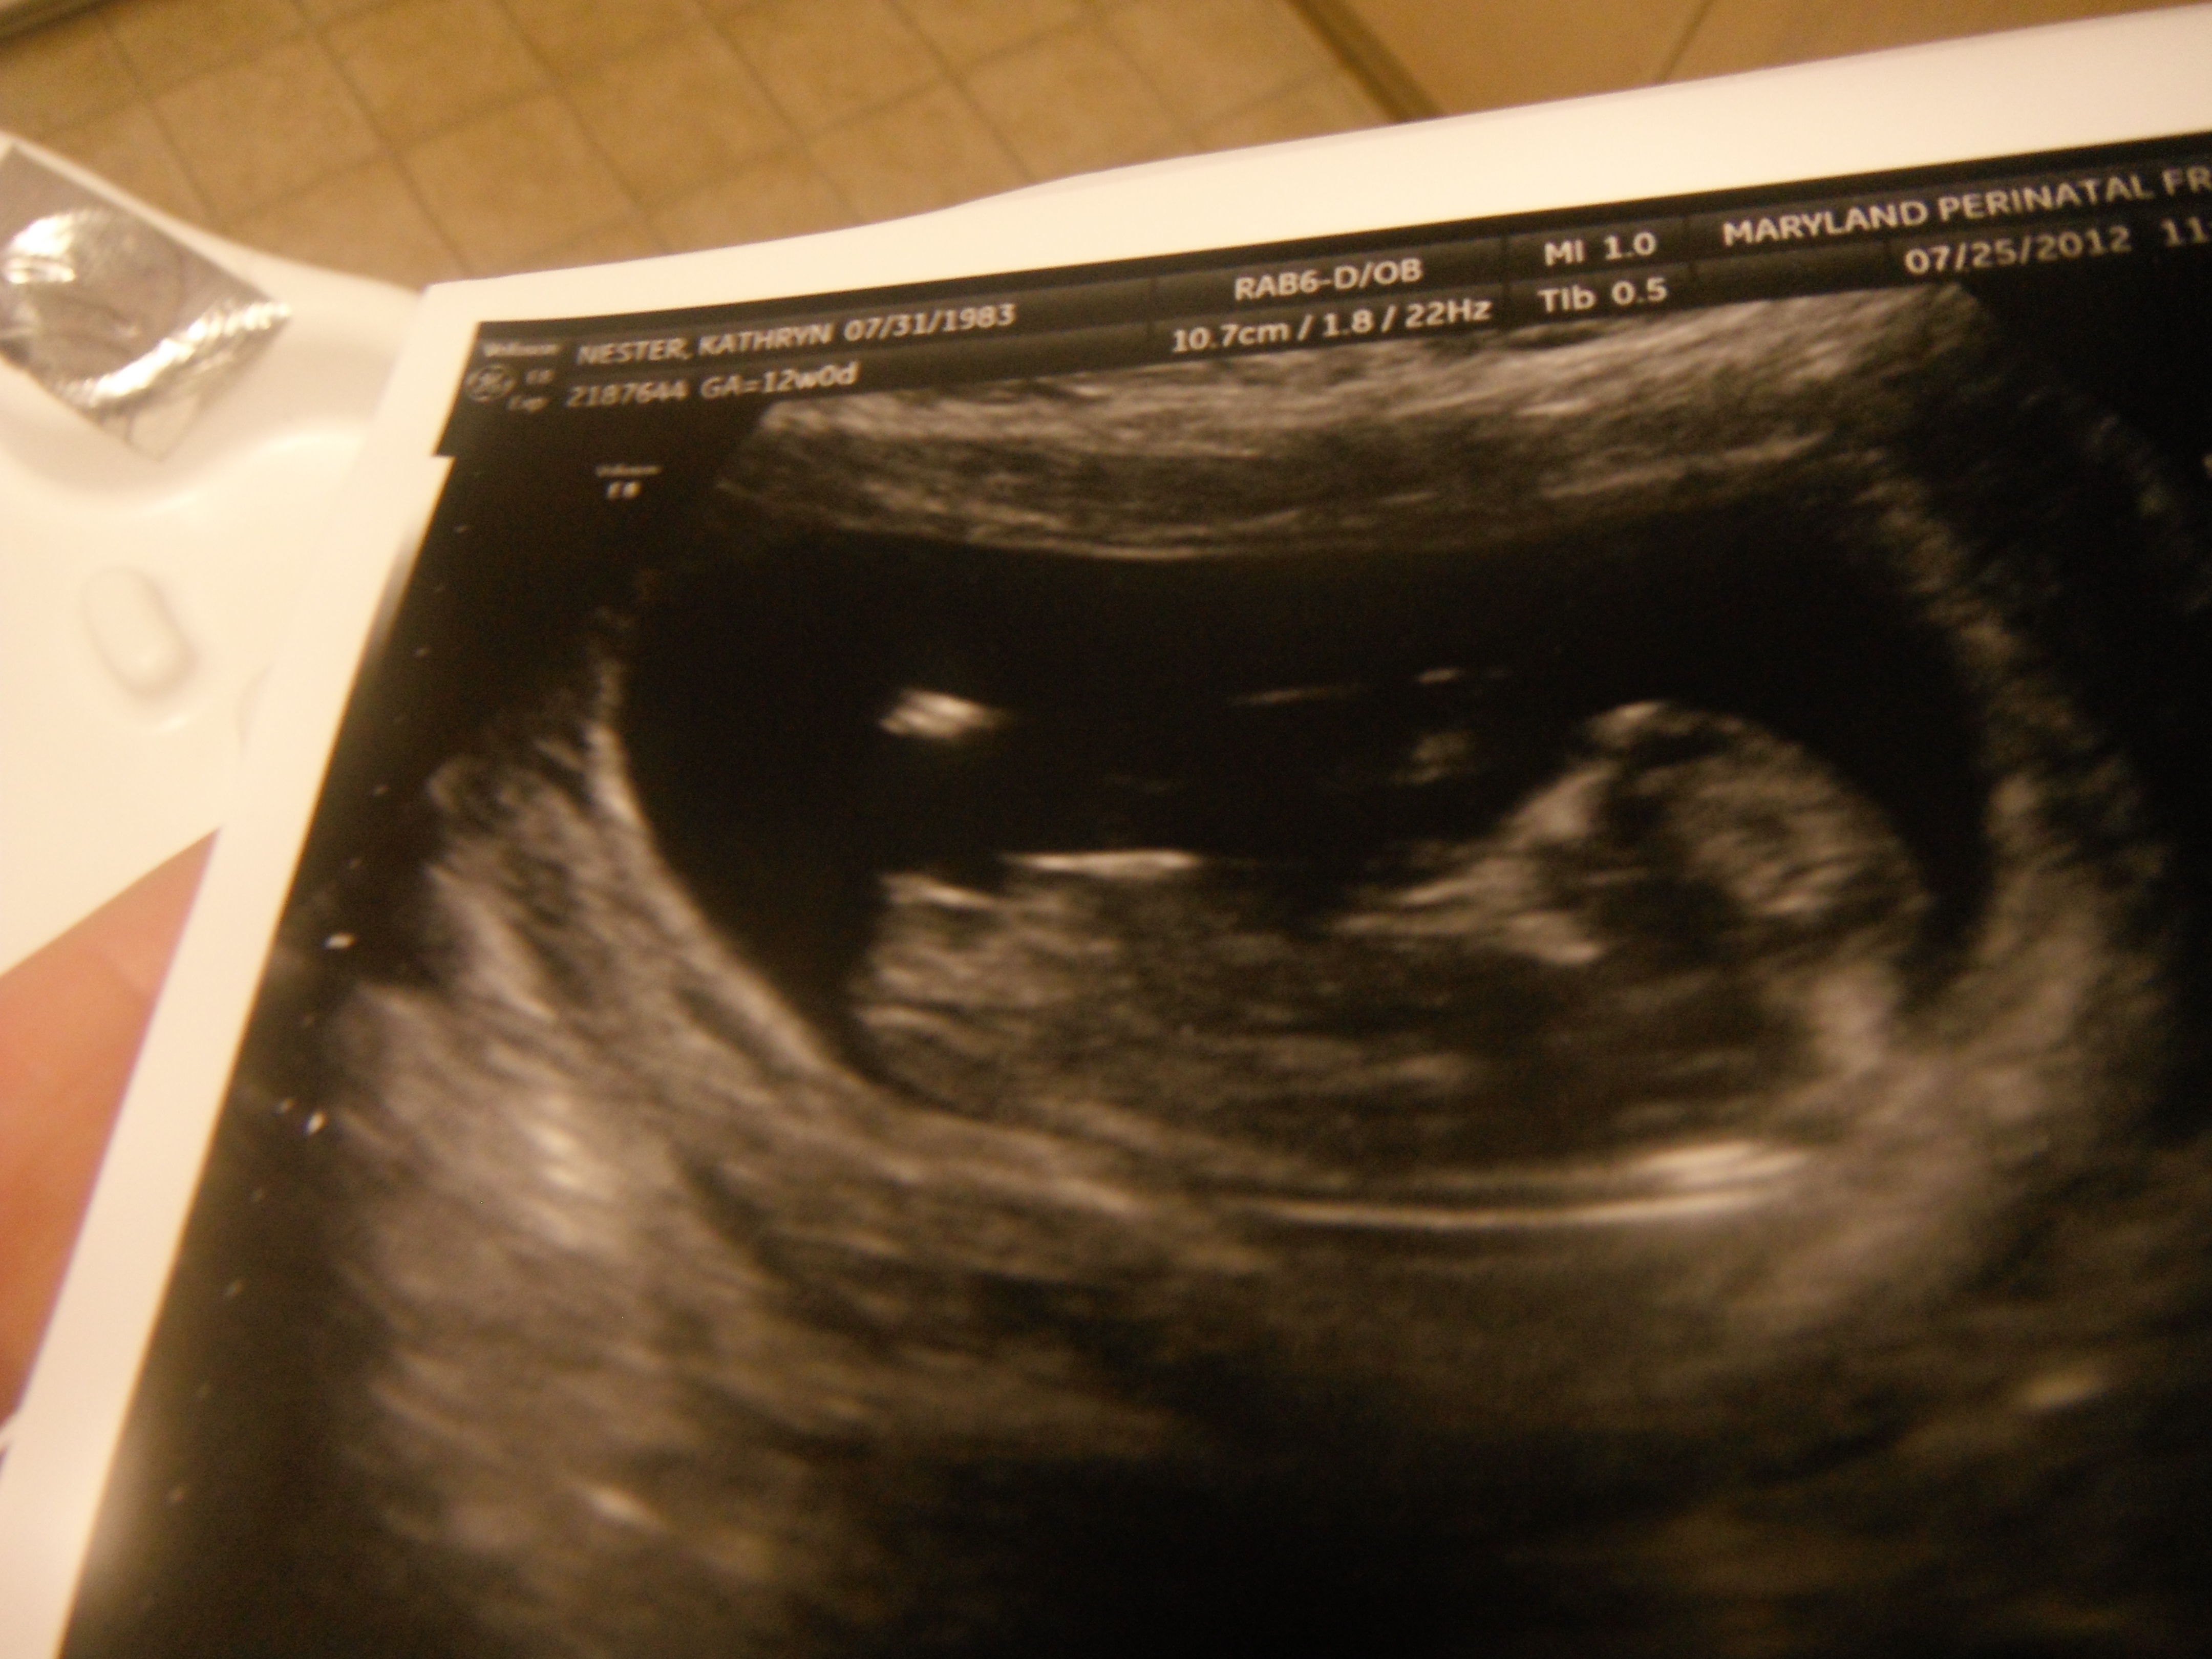

would love a NUB GUESS on our "whoops we got pregnant before we could sway" baby! :)

Atomic, I said I'd be back with gender... though at 12 weeks it's just a guess... ;)

Tech didn't want to say anything - but after I coerced her...she said, "Initially I thought I saw boy parts, then as the scan went on, I mentally changed my guess."

Hard to tell so early...but is anyone else brave enough to give me their thoughts?